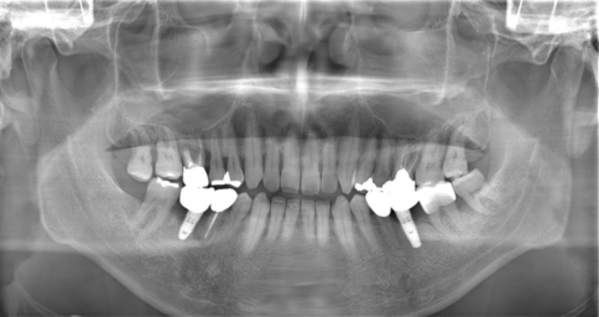

こちらは初診時のパノラマX線写真です。

(写真は左側が右の歯、右側が左の歯となります)

主訴となった右下6番部のインプラント周囲は、明らかにインプラント周囲炎を起こしており、骨が大きく喪失(吸収)していました。痛みはほとんどありませんでしたが、出血、排膿、腫れ、臭いなどの自覚症状が強くみられました。

しかし問題はそれだけではありません。

反対側の左下6番部インプラントにもすでにインプラント周囲炎と診断できる状態が認められ、さらに全顎的に歯周病の進行が著しい状況でした。